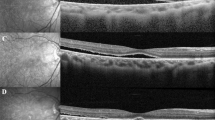

The presence of SRF and postoperative ERM were recognized and determined by OCT examination, which was performed with 5LineCross and 3D scan mode. Scan length and width were 9.0 mm × 9.0 mm with horizontal and vertical direction. SRF was defined as exudate or fluid between the neurosensory retina and the RPE in the fovea. Postoperative ERM was defined as hyper-reflective line above the inner surface of macular, and ERM at stage 3 or stage 4 was included in the present study. The demographic characteristics were collected, including age, gender, and symptom duration. The clinical features at the first presentation and every postoperative follow-up visit was abstracted for use in this study. Statistical analysis was performed using SPSS (version 20.0, Chicago, IL, USA). The values of continuous variables (age, symptom duration, BCVA, and IOP) were presented as mean ± standard deviation (SD). After been tested for normal distribution, the BCVA, IOP and age were compared with independent t-test, while symptom duration was compared with Mann–Whitney U-test. Categorical variables were presented as the number of subjects and its percentage, and the difference was analyzed by Chi-square test or Fisher exact test. A Kaplan–Meier graph comparing survival time of SRF for the air injection group and no air injection group was plotted. Binary Logistic Regression was used to investigate the associated factors for the persistent SRF. p Value < 0.05 was considered statistically significant.